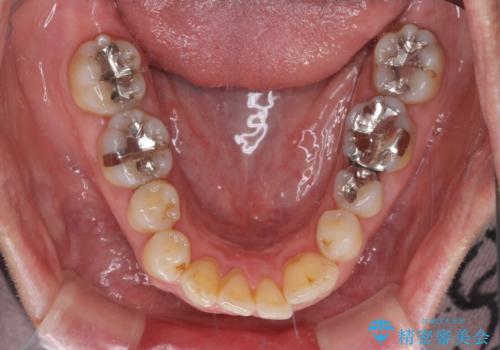

八重歯と形の悪い前歯 矯正治療とセラミック治療

- 長年前歯の歯並びで悩んでいるとのことで来院された患者様です。

機能的なことを考えると八重歯となっている犬歯は抜歯せず、歯列を改善することが望ましいとされますが、数十年もの間犬歯がない咬み合わせで問題なく過ごしてきたため、八重歯を抜歯することで、手っ取り早く歯列を改善することとしました。